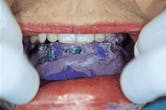

Figure 3-After the diagnostic denture has satisfied all of the patient`s needs for esthetics, comfort and function, a clear duplicate of the mandibular denture is constructed. These are very accurate duplicates, and the vertical dimension, centric relation and tooth position can be verified in the mouth. If the implants have not been placed, then this clear duplicate is used as the surgical guide.

Figure 3